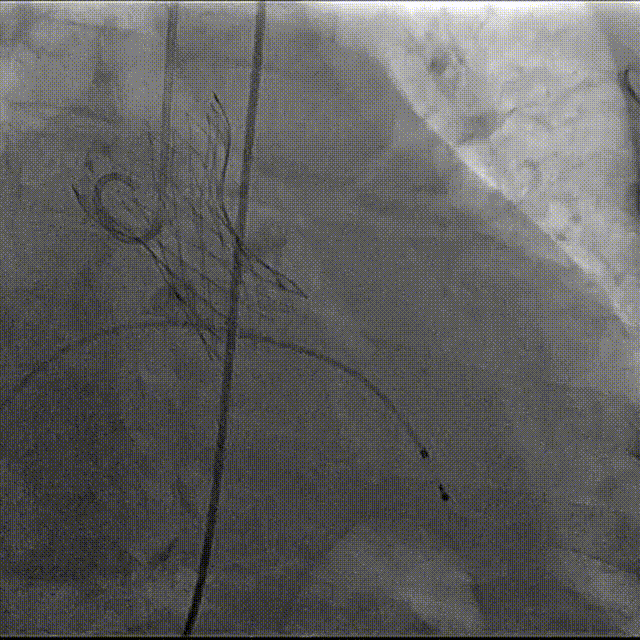

导丝跨瓣

23mm球囊预扩